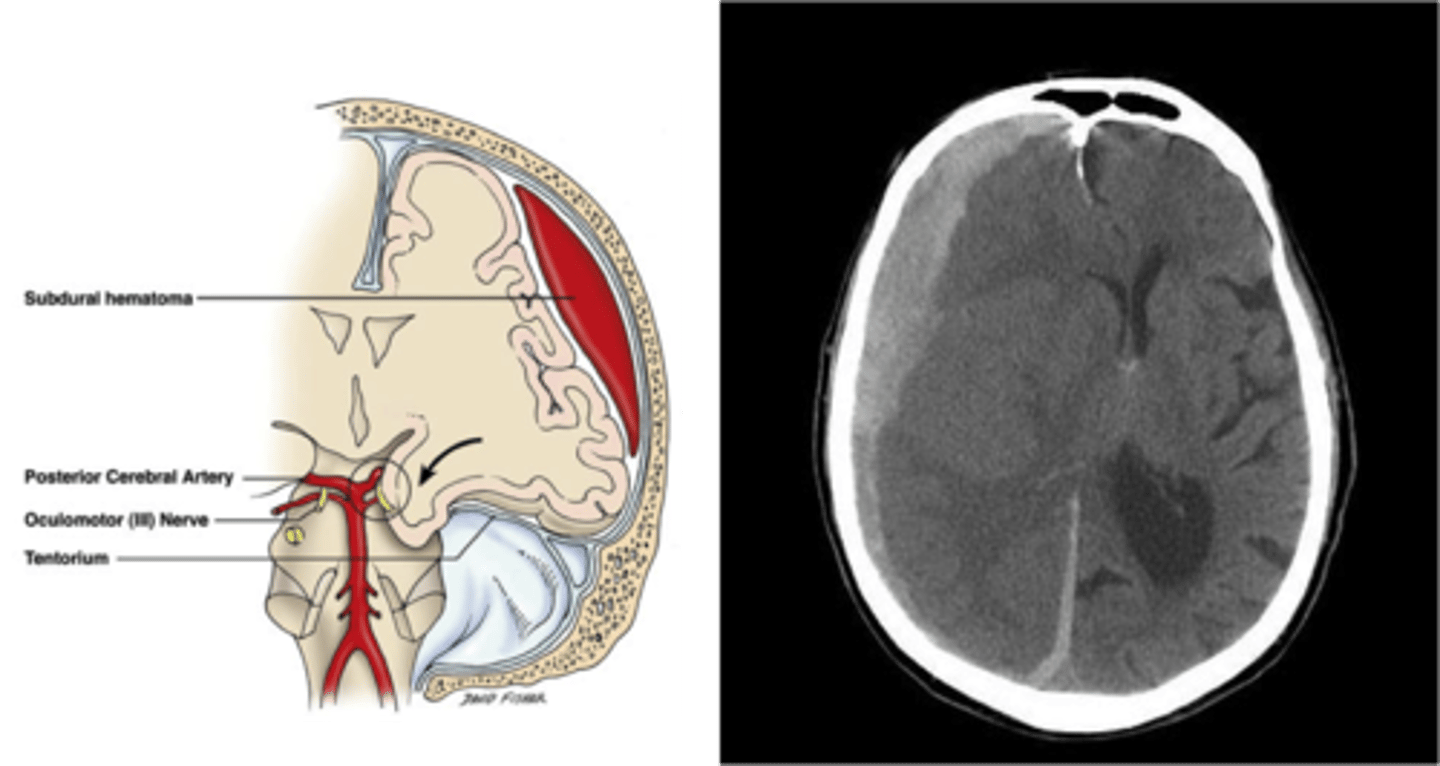

Effect of brain movement which may tear small arteries and cause subdural hemorrhages (letter D in the image)

Subdural hemorrhage

Bleeding between dura and arachnoid membrane as a result of rupture of cortical veins that bridge the subdural space; spreads thinly and widely until it is limited by dural barriers